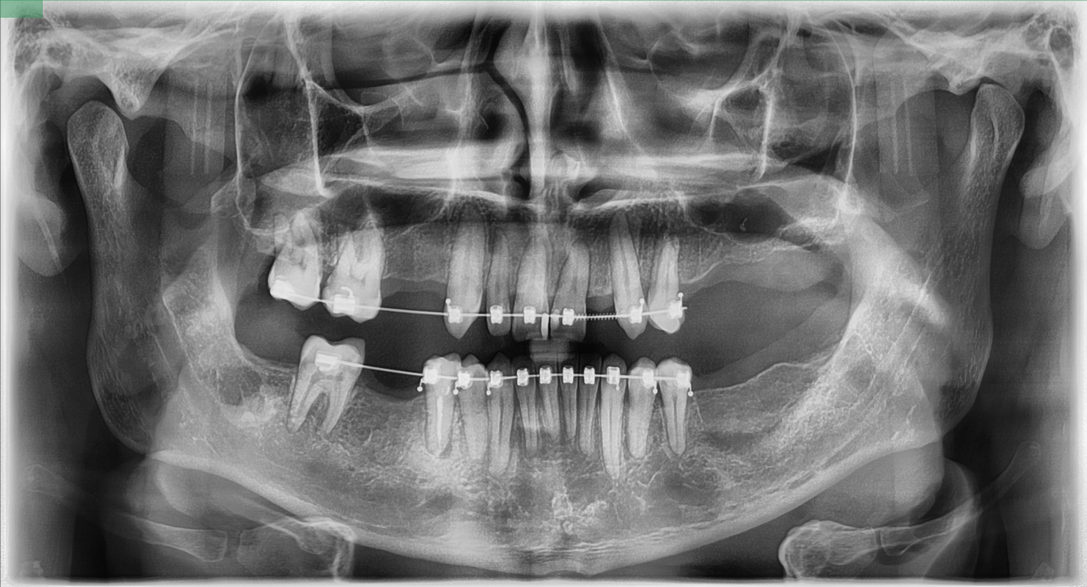

Лечение Артема начали с удаления поврежденных зубных единиц. За один визит под общим наркозом удалили зубы 1.4, 1.5, 1.8, 2.5, 2.6, 2.7, 3.8, 4.8. После заживления зафиксировали брекет-систему на верхнюю и нижнюю челюсти. Задача ортодонтического лечения в данном случае — сформировать место для установки имплантатов для восстановления отсутствующих зубов и восстановить правильное положение резцов.

Место для зуба 2.2 сформировано, резцы верхней и нижней челюсти занимают правильное положение

Брекеты не помешают имплантации. Во время операции и в течение всего периода приживления имплантатов Артем будет продолжать ортодонтическое лечение.